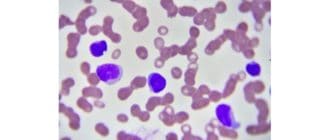

好塩基球増加症は、人の血液中に好塩基球が多すぎる場合を指します。好塩基球は白血球の一種である。 好塩基球増加症はそれ自身の状態ではないが、他の根底にある医学的問題の重要なマーカーとなりうる。 好塩基球とは何ですか? 健康 […]